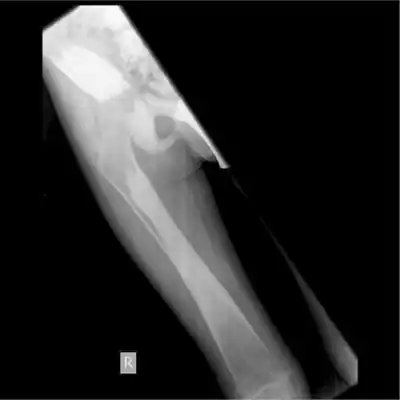

Camurati–Engelmann disease (CED) is a very rare autosomal dominant genetic disorder that causes characteristic anomalies in the skeleton. It is also known as progressive diaphyseal dysplasia. It is a form of dysplasia.[3] Patients typically have heavily thickened bones, especially along the shafts of the long bones (called diaphyseal dysplasia). The skull bones may be thickened so that the passages through the skull that carry nerves and blood vessels become narrowed, possibly leading to sensory deficits, blindness, or deafness.

Patients with CED complain of chronic bone pain in the legs or arms, muscle weakness (myopathy) and experience a waddling gait. Other clinical problems associated with the disease include increased fatigue, weakness, muscle spasms, headache, difficulty gaining weight, and delay in puberty. Some patients have an abnormal or absent tibia, may present with a flat foot, or scoliosis.[1]

This disease may also cause bones to become abnormally hardened which is referred to as sclerosis. This hardening may affect the bones at the base of the skull or those in the hands, feet, or jaw. This causes ongoing pain and aching within the body parts that are affected. The pain has been described as either a hot electric stabbing pain, an ever-increasing pressure sensation around the bones (especially before electrical storms) or as a constant ache that radiates through several long bones at once. Pain may also occur in the hips, wrists, knees and other joints as they essentially just 'lock-up' (often becoming very stiff, immobile and sore), mostly when walking up or down staircases, writing for extended periods of time, or during the colder months of the year. Those with the disease tend to have a very characteristic walk medically diagnosed as a 'waddling gait'. This is observed by the broad-based gait with a duck-like waddle to the swing phase, the pelvis drops to the side of the leg being raised, notable forward curvature of the lumbar spine and a marked body swing.[5][6]